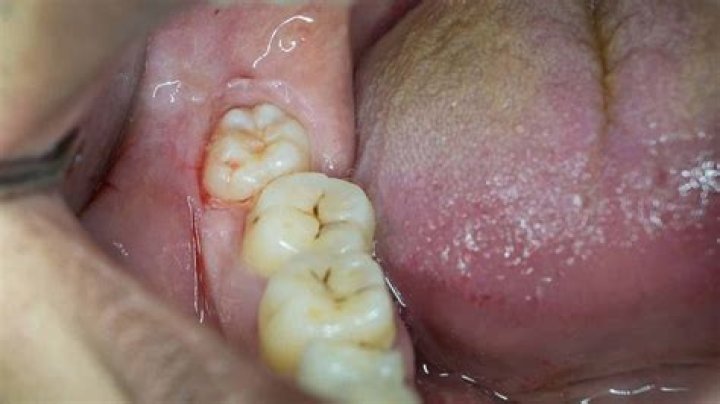

Are wisdom teeth painful?

If your wisdom teeth have enough space, and if they grow in straight, you might not ever feel pain. However, if your wisdom teeth erupt and there isn't enough room for them in your mouth, they typically cause intense pain, inflammation, and irritation.

Wisdom tooth pain is usually quite intense. It often feels like pain in the back of your mouth or at your jaw. Other people experience throbbing feelings or pressure in the back of their mouths. Cut or swollen gums also possibly indicate wisdom teeth trying to break through into your mouth.

Wisdom teeth usually emerge sometime between the ages of 17 and 25. Some people have wisdom teeth that emerge without any problems and line up with the other teeth behind the second molars. In many cases, however, the mouth is too crowded for third molars to develop normally.

Wisdom teeth normally start to erupt between the ages of 17 and 25. However, the process does not happen at the same pace for everyone. In fact, it can take years for the wisdom teeth to fully emerge through the gums or they may never erupt at all.